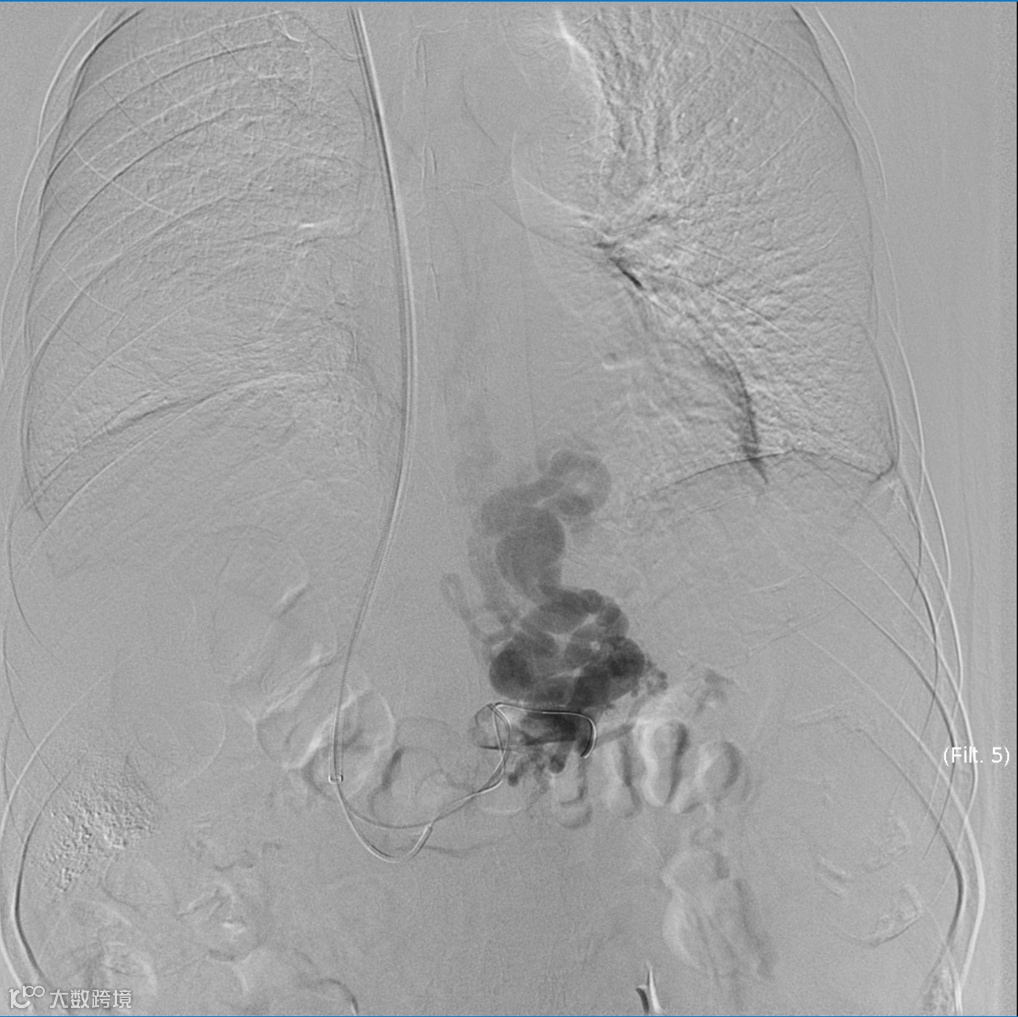

建立门体静脉分流道后行门静脉、脾静脉造影

胃冠状静脉造影

超选择插入至曲张静脉,注入弹簧圈栓塞至血流明显减缓

超选择插入至曲张静脉,注入弹簧圈栓塞,后经微导管注入聚桂醇至曲张静脉血流基本停滞

后续手术,其它器械操作:分流道成形

术后造影(即刻效果):胃底曲张静脉血管网未见显影